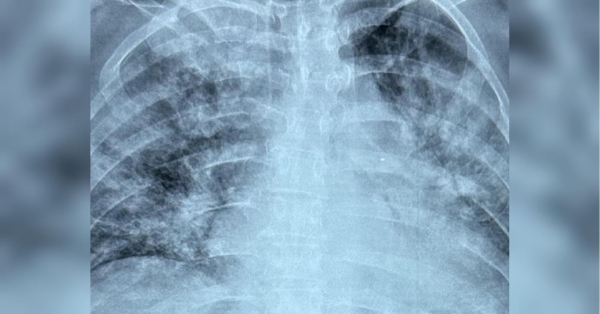

Ковід плюс грип — смертельний тандем: інфекціоністка дала важливі рекомендації щодо зростання захворюваності в Україні

В Україні зросла захворюваність на респіраторні інфекції. Часто грип поєднується із коронавірусною інфекцією. Про це повідомила головний позаштатний інфекціоніст Міністерства охорони здоров’я України доктор медичних наук професор Ольга Голубовська.

«Шановні колеги та друзі, дуже велика кількість хворих на грип, у т.ч. тяжких, у т.ч. із коінфекцією ковід+грип. Зростає летальність. На жаль, як завжди, всі летальні випадки обумовлені відсутністю специфічної терапії в перші дні хвороби», — написала вона.

Як писали «ФАКТИ», наприкінці минулого року за два місяці від COVID-19 померли понад 300 українців, серед них двоє дітей. Всесвітня організація охорони здоров’я повідомила про різке зростання випадків зараження коронавірусом за останній місяць.